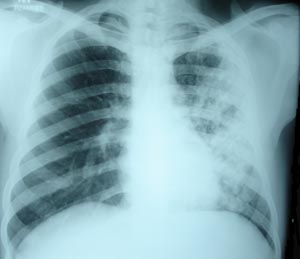

Left mid zone Koch’s infection 3

Right mid zone shows multiple fibronodular opacity, suggestive of unilateral koch’s infiltration. There is some improvement. Patient on 4 drug AKT regimen. Symptoms have disappered.